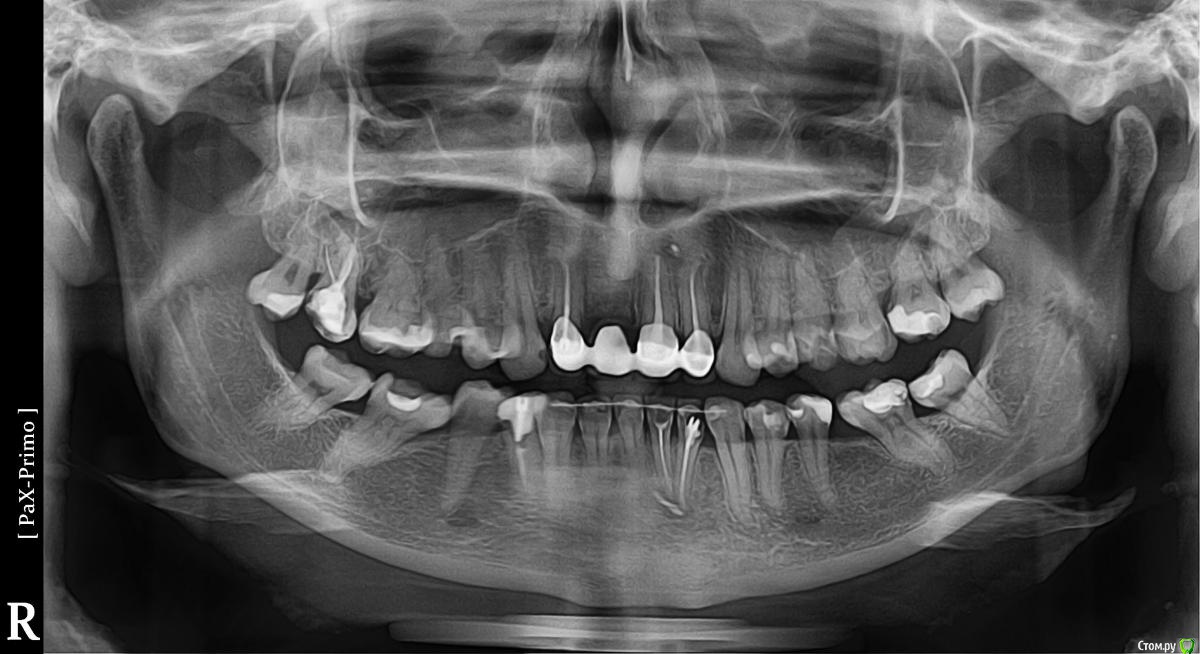

Koloss Опубликовано 18 сентября, 2015 Поделиться Опубликовано 18 сентября, 2015 Здравствуйте, уважаемые доктора! Ставлю коронку на 4-й нижний зуб справа. Этот зуб лечился и депульпировался около 7 лет назад, все это время был под пломбой. Врач решил не перепломбировать канал, не менять штифт, говорит: штифт стоит крепко (хоть и коротковат) , зуб не беспокоит, и на снимках не видно корня - лучше его не трогать раз не беспокоит. Как Вы считаете как лучше поступить с этим зубом и почему нижние правые 1-4 корни зубов на панорамных снимках такие размытые? Нижние зубы от клыка до клыка зашинированы после брекетов. Спасибо Ссылка на комментарий

Koloss Опубликовано 18 сентября, 2015 Автор Поделиться Опубликовано 18 сентября, 2015 Спасибо, большое за ответы. Скажите, пожалуйста, почему нижние правые 1-4 корни зубов на панорамных снимках размытые, на остальных зубах ведь четкие? С этими зубами порядок? Ссылка на комментарий

St. Опубликовано 18 сентября, 2015 Поделиться Опубликовано 18 сентября, 2015 Спасибо, большое за ответы. Скажите, пожалуйста, почему нижние правые 1-4 корни зубов на панорамных снимках размытые, на остальных зубах ведь четкие? С этими зубами порядок?Да, это особенность панорамных снимков. Ссылка на комментарий